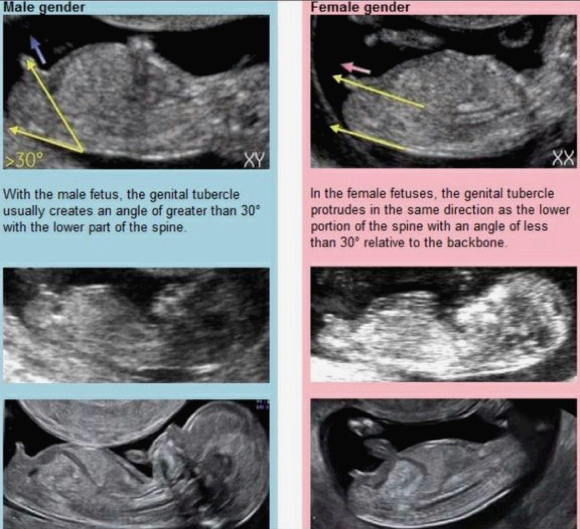

7. 각도법 : 임신 12주차에 초음파로 본 생식기의 위치로, 척추 아랫부분 기준 평행이면 딸 <> 30도 이상 솟아(?) 있으면 아들 (튼튼이의 초음파 사진에는 생식기가 다리로 가려져 있어서 이 역시 패스 ㅠ)